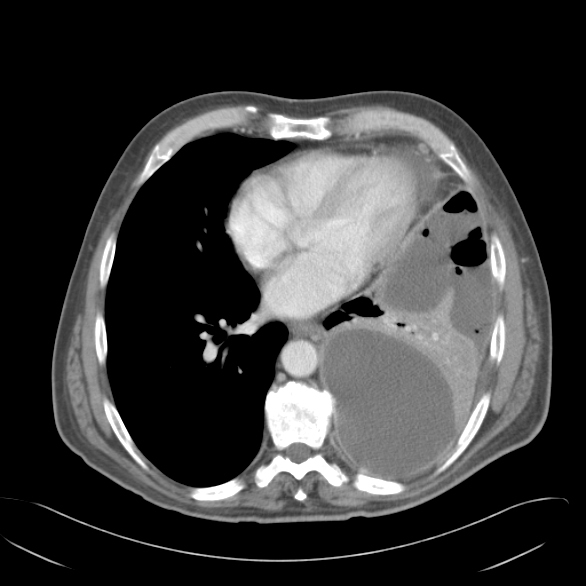

CT scan of the chest provides information on the location, degree of loculation, the extent of the empyema, and the underlying lung parenchyma (Figure 1). It is not unusual for an organism not to be identified on the pleural fluid culture and therefore broad-spectrum antibiotic coverage should be instituted when the diagnosis of empyema is made. This can be modified if the culture data identifies an organism. The antibiotics are continued for the perioperative period.

Once the chest is entered, a Yankauer suction is used to drain the chest of effusion or blood (Video 3, Video 4 below) and along with a finger used to break up simple loculations (Video 5 below). The preoperative CT scan helps guide this ‘blind’ initial drainage and creates a working pleural space for the thoracoscopic instruments. Gelatinous fibrinous deposits and blood clots are removed with a curved ring forceps clips (Video 6, Video 7 below). The visceral pleural peel can be debrided using ring-forceps, a curette (Video 8 below) and a peanut dissector as in an open decortication.

Thoracoscopic decortication is now proven in the management of empyema and the time elapsed since the origin of the empyema and the surgical intervention is probably most predictive of the ability to perform the operation successfully [3, 7]. CT scan is not useful in this respect but helps with port placement and the direction of the decortication within the chest [4]. The principles of open decortication should be followed while utilizing thoracoscopic technology. All areas of fibrinous material must be drained and the underlying lung freed from a restricting pleural peel to allow for complete re expansion. Success rates are high and chest tube duration, hospital length of stay, postoperative pain, and recovery are improved over thoracotomy. Mortality rates are low as are recurrent rates and complications [2-4, 7-9]. Conversions to open thoracotomy are more frequent than after other thoracoscopic procedures, but this should be considered an exercise of sound surgical judgment rather than a failure of the technique.